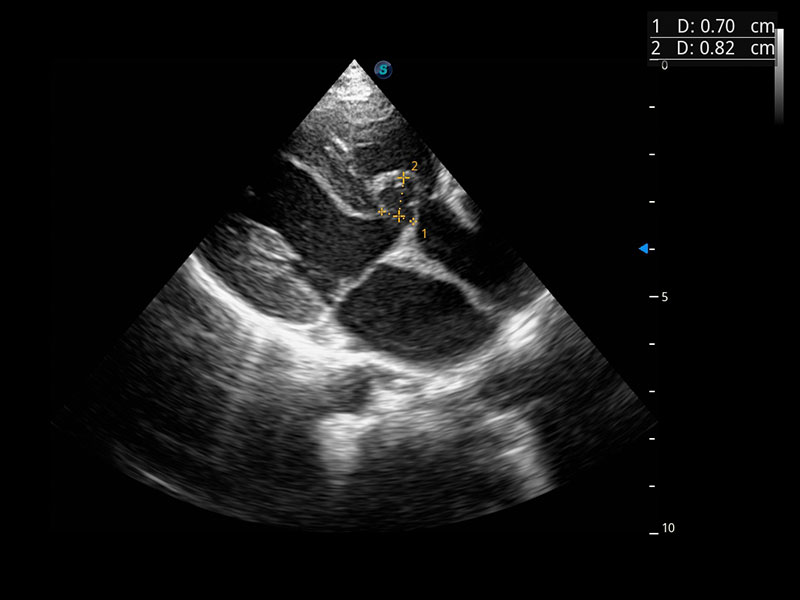

Cardiovascolare avanzato

Si impegna a fornire una soluzione completa per la valutazione cardiaca

Dotato dell'esclusivo trasduttore a cristallo singolo SonoScape e di una tecnologia di elaborazione all'avanguardia, P60 si impegna a ripristinare ogni dettaglio ed elemento per una diagnosi precisa. La nuova analisi quantitativa del miocardio (MQA) fornisce un referto quantitativo approfondito sulle dinamiche del movimento della parete miocardica globale e regionale del ventricolo sinistro, offrendo ai medici una valutazione completa delle funzioni miocardiche.

• Stress Echo

• MQA con analisi della deformazione

• TDI (Tissue Doppler Imaging)

• Opacizzazione VS

• Auto EF

Trasduttori estesi